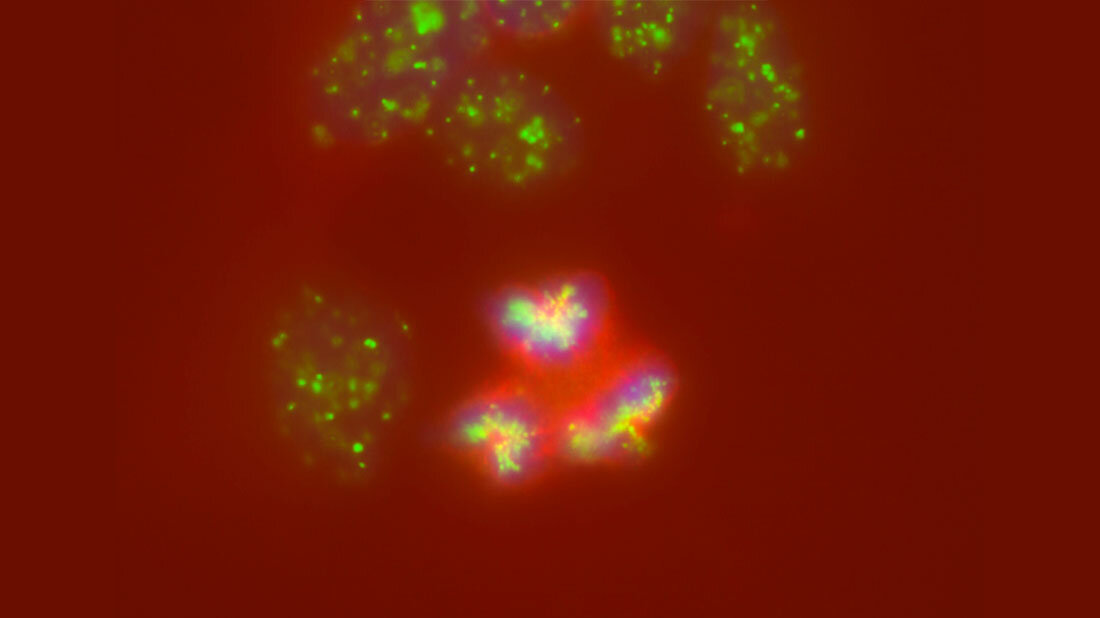

Dafür entschlüsselten die Wissenschaftler/-innen das Tumorgenom von 100 Patientinnen und Patienten mit Neuroblastomen unterschiedlicher Stadien. Anschließend rekonstruierten sie anhand bestimmter Erbgutveränderungen die Entstehungsgeschichte der Tumoren. „Man geht davon aus, dass sich Erbgutveränderungen in unserem Genom zufällig und über die Zeit hinweg mit konstanter Geschwindigkeit wie Sand in einer Sanduhr anhäufen“, erklärt die Erstautorin der Studie Verena Körber aus der Arbeitsgruppe für theoretische Systembiologie von Thomas Höfer am DKFZ. „Das wird auch als molekulare Uhr bezeichnet und ist messbar. Mit Hilfe eines speziell dafür entwickelten mathematischen Modells konnten wir daraus einen Stammbaum der Neuroblastom-Entstehung rekonstruieren“, sagt Körber weiter.